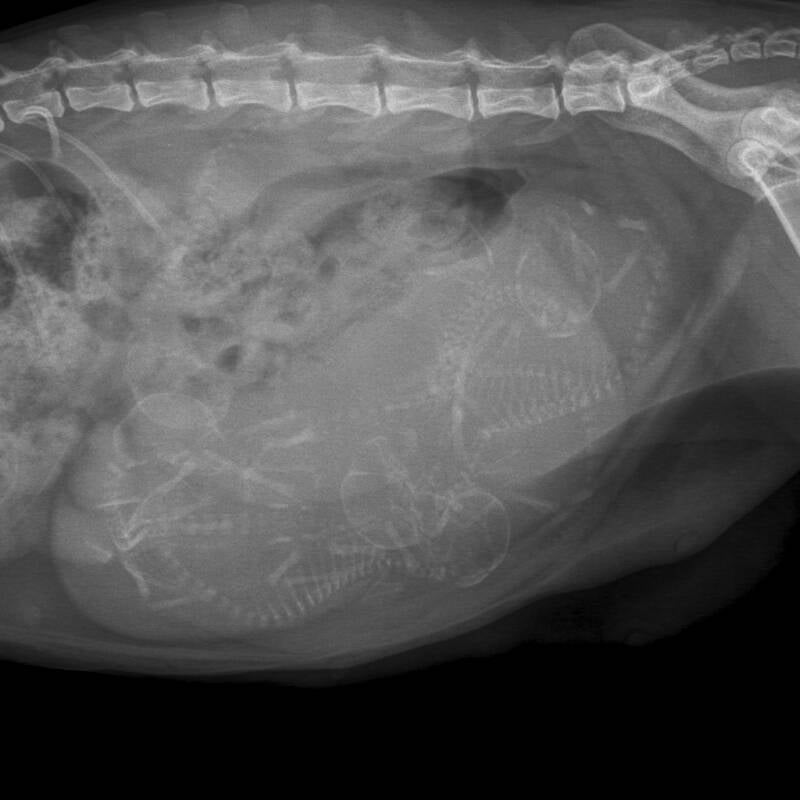

Foto 21 17-03-2019 en foto 22 20-03-2019

Foto 21 (60 dagen) en Foto 22 ( 63 dagen)

Vandaag een dracht foto laten maken omdat we wilde kijken hoe de kittens lagen (er liggen er 2 bij de uitgang waarvan 1 in stuit. Gezien haar vorige bevalling niet vlekkeloos verliep (de voorste lag dwars en daardoor kon ze niet via de normale weg bevallen) hebben we op voorhand een foto laten maken. Ze is drachtig van 6 kittens en omdat niet duidelijk is wat de 2 kittens voor de uitgang gaan doen hebben we vanaf volgende week dagelijks contact met onze dierenarts. We hopen echt dat een keizersnede haar bespaard zal blijven.